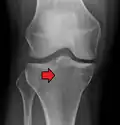

In all injuries to the tibial plateau radiographs (commonly called x-rays) are imperative. Computed tomography scans are not always necessary but are sometimes critical for evaluating degree of fracture and determining a treatment plan that would not be possible with plain radiographs.[10] Magnetic Resonance images are the diagnostic modality of choice when meniscal, ligamentous and soft tissue injuries are suspected.[11][12] CT angiography should be considered if there is alteration of the distal pulses or concern about arterial injury.

Subtle tibial plateau fracture on an AP X ray of the knee -

A tibial plateau fracture seen on X-ray